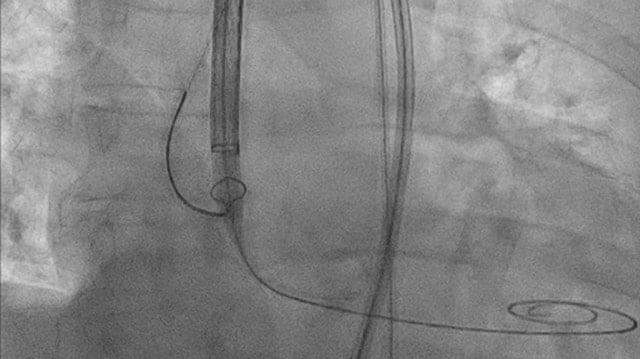

A challenging valve-in-valve scenario in a patient with prior aortic coarctation repair

A 79-year-old with a degenerated aortic bioprosthesis after complex coarctation surgery challenges conventional strategies. Which access route would you choose?